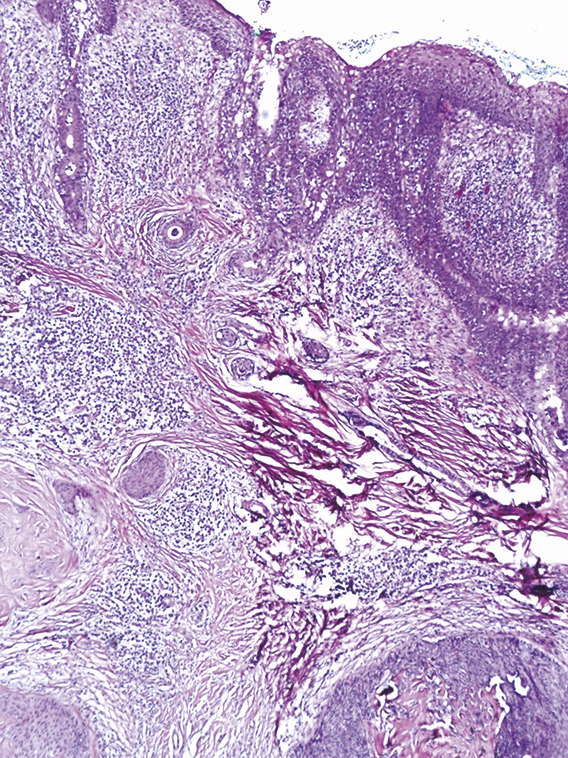

Cet homme de 40 ans, suivi pour un retard mental, consultait pour un placard papuleux blaschko-linéaire, s’étendant de la région médiocervicale à la région temporopariétale gauche évoluant depuis son bas âge, associé à de multiples nodules érythémateux suintants de la joue gauche et du cuir chevelu ainsi qu’à une lésion ulcéro-croûteuse frontale gauche (fig. 1 ). L’étude histologique montrait un hamartome sébacé et quatre tumeurs distinctes : un syringocystadénome, une tumeur combinée associant un syringocystadénome papillifère et un hidradénome, un trichoépithéliome et un carcinome basocellulaire nodulaire (fig. 2 et 3 ). L’examen ophtalmologique et l’IRM craniocérébrale étaient normaux. Le diagnostic d’un syndrome de Schimmelpenning-Feuerstein-Mims compliqué de tumeurs annexielles et d’un basocellulaire était retenu et le patient adressé en chirurgie maxillofaciale pour sa prise en charge.

L’hamartome sébacé est une malformation congénitale atteignant typiquement la tête et le cou. Il peut s’accompagner de malformations complexes dans le cadre du syndrome de Schimmelpenning- Feuerstein-Mims.1 Ce dernier correspond à l’association d’un nævus sébacé et de diverses malformations, oculaires, neurologiques notamment un retard mental. Le développement classique de tumeurs bénignes sur nævus sébacé est rapporté dans la littérature alors que les tumeurs malignes sont plus rares, dominées par le carcinome basocellulaire.2 Le traitement de choix est la chirurgie. Des alternatives peuvent être proposées, notamment la dermabrasion, le laser CO2 et la photothérapie dynamique.